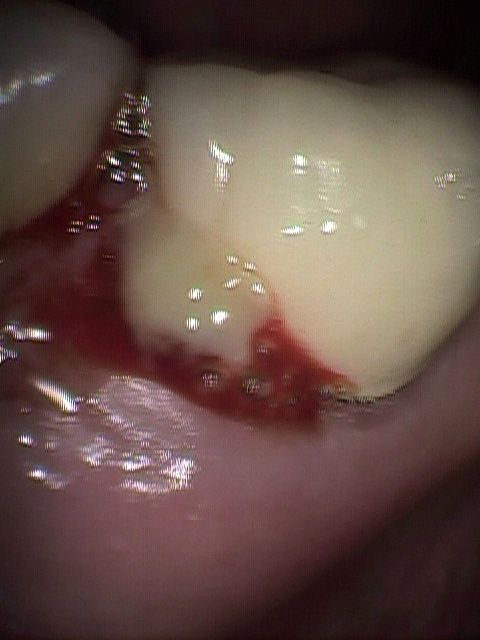

Photo-1

【歯周病も重症になるとブラッシングだけでは、このように出血の改善はみられず、細菌の制御(殺滅・除去)とレーザー治療が必要

上記、重症の歯周病のポケットから採取された大量のrodやT.d菌。